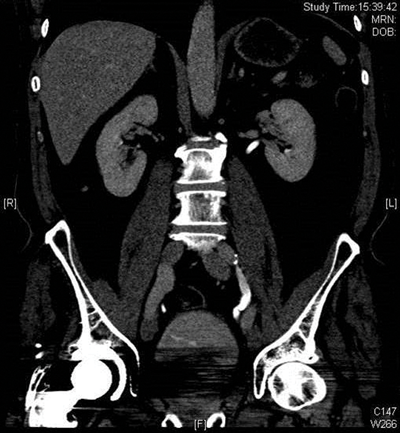

The collecting systems and ureters should be opacified on the excretory phase of CT urogram and adequate distension and opacification of the ureter and pelvicalyceal system are vital when evaluating the urothelium. Filling defects can be difficult to appreciate on abdominal windows and subtle filling defects are more clearly seen on bone window settings. This can allow ureteric neoplasms to be distinguished from other causes of filling defects. Figure 4 shows an example of a filling defect in the left ureter that is more clearly defined on bone windows compared with abdominal windows. This was a female patient who presented with cyclic pain and was found on biopsy to have endometriosis in the left ureter.

Figure 4a: Abdominal windows filling defect.

Figure 4b: Bone windows filling defect.